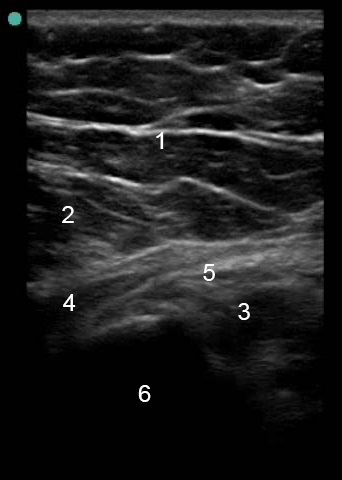

Imagen anatómica de la bolsa trocantérica en el lateral la cadera

1. Grasa subcutánea

2. Músculo glúteo mayor

3. Músculo glúteo medio

4. Músculo tensor de la fascia lata

5. Interfase bursal

6. Corteza del trocánter mayor